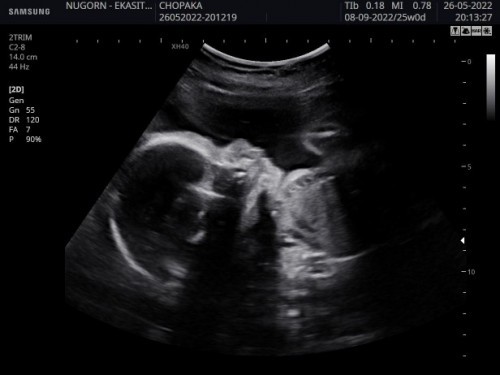

สาวน้อย 1 กันยาค่าา 26+3 สัปดาห์